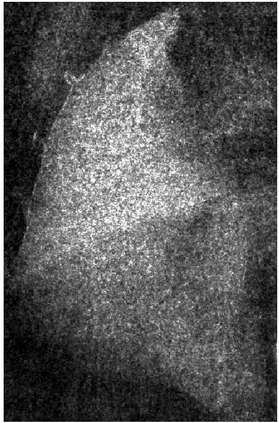

Low-dose computed tomography (LDCT) is the current standard for lung cancer screening, yet its adoption and accessibility remain limited. Many regions lack LDCT infrastructure, and even among those screened, early-stage cancer detection often yield false positives, as shown in the National Lung Screening Trial (NLST) with a sensitivity of 93.8 percent and a false-positive rate of 26.6 percent. We aim to investigate whether X-ray dark-field imaging (DFI) radiograph, a technique sensitive to small-angle scatter from alveolar microstructure and less susceptible to organ shadowing, can significantly improve early-stage lung tumor detection when coupled with deep-learning segmentation. Using paired attenuation (ATTN) and DFI radiograph images of euthanized mouse lungs, we generated realistic synthetic tumors with irregular boundaries and intensity profiles consistent with physical lung contrast. A U-Net segmentation network was trained on small patches using either ATTN, DFI, or a combination of ATTN and DFI channels.Results show that the DFI-only model achieved a true-positive detection rate of 83.7 percent, compared with 51 percent for ATTN-only, while maintaining comparable specificity (90.5 versus 92.9 percent). The combined ATTN and DFI input achieved 79.6 percent sensitivity and 97.6 percent specificity. In conclusion, DFI substantially improves early-tumor detectability in comparison to standard attenuation radiography and shows potential as an accessible, low-cost, low-dose alternative for pre-clinical or limited-resource screening where LDCT is unavailable.